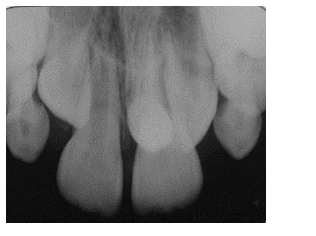

Uma criança de oito anos de idade foi ao dentista, pela primeira vez, para consulta de rotina. Mediante análise do exame radiográfico periapical dos dentes anterossuperiores, encontrou-se um mesiodens. Considerando essa situação e a(s) técnica(s) de localização radiográfica, julgue os itens a seguir.